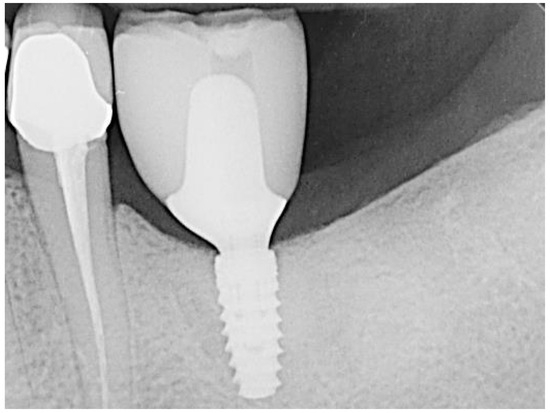

2. Materials and Methods